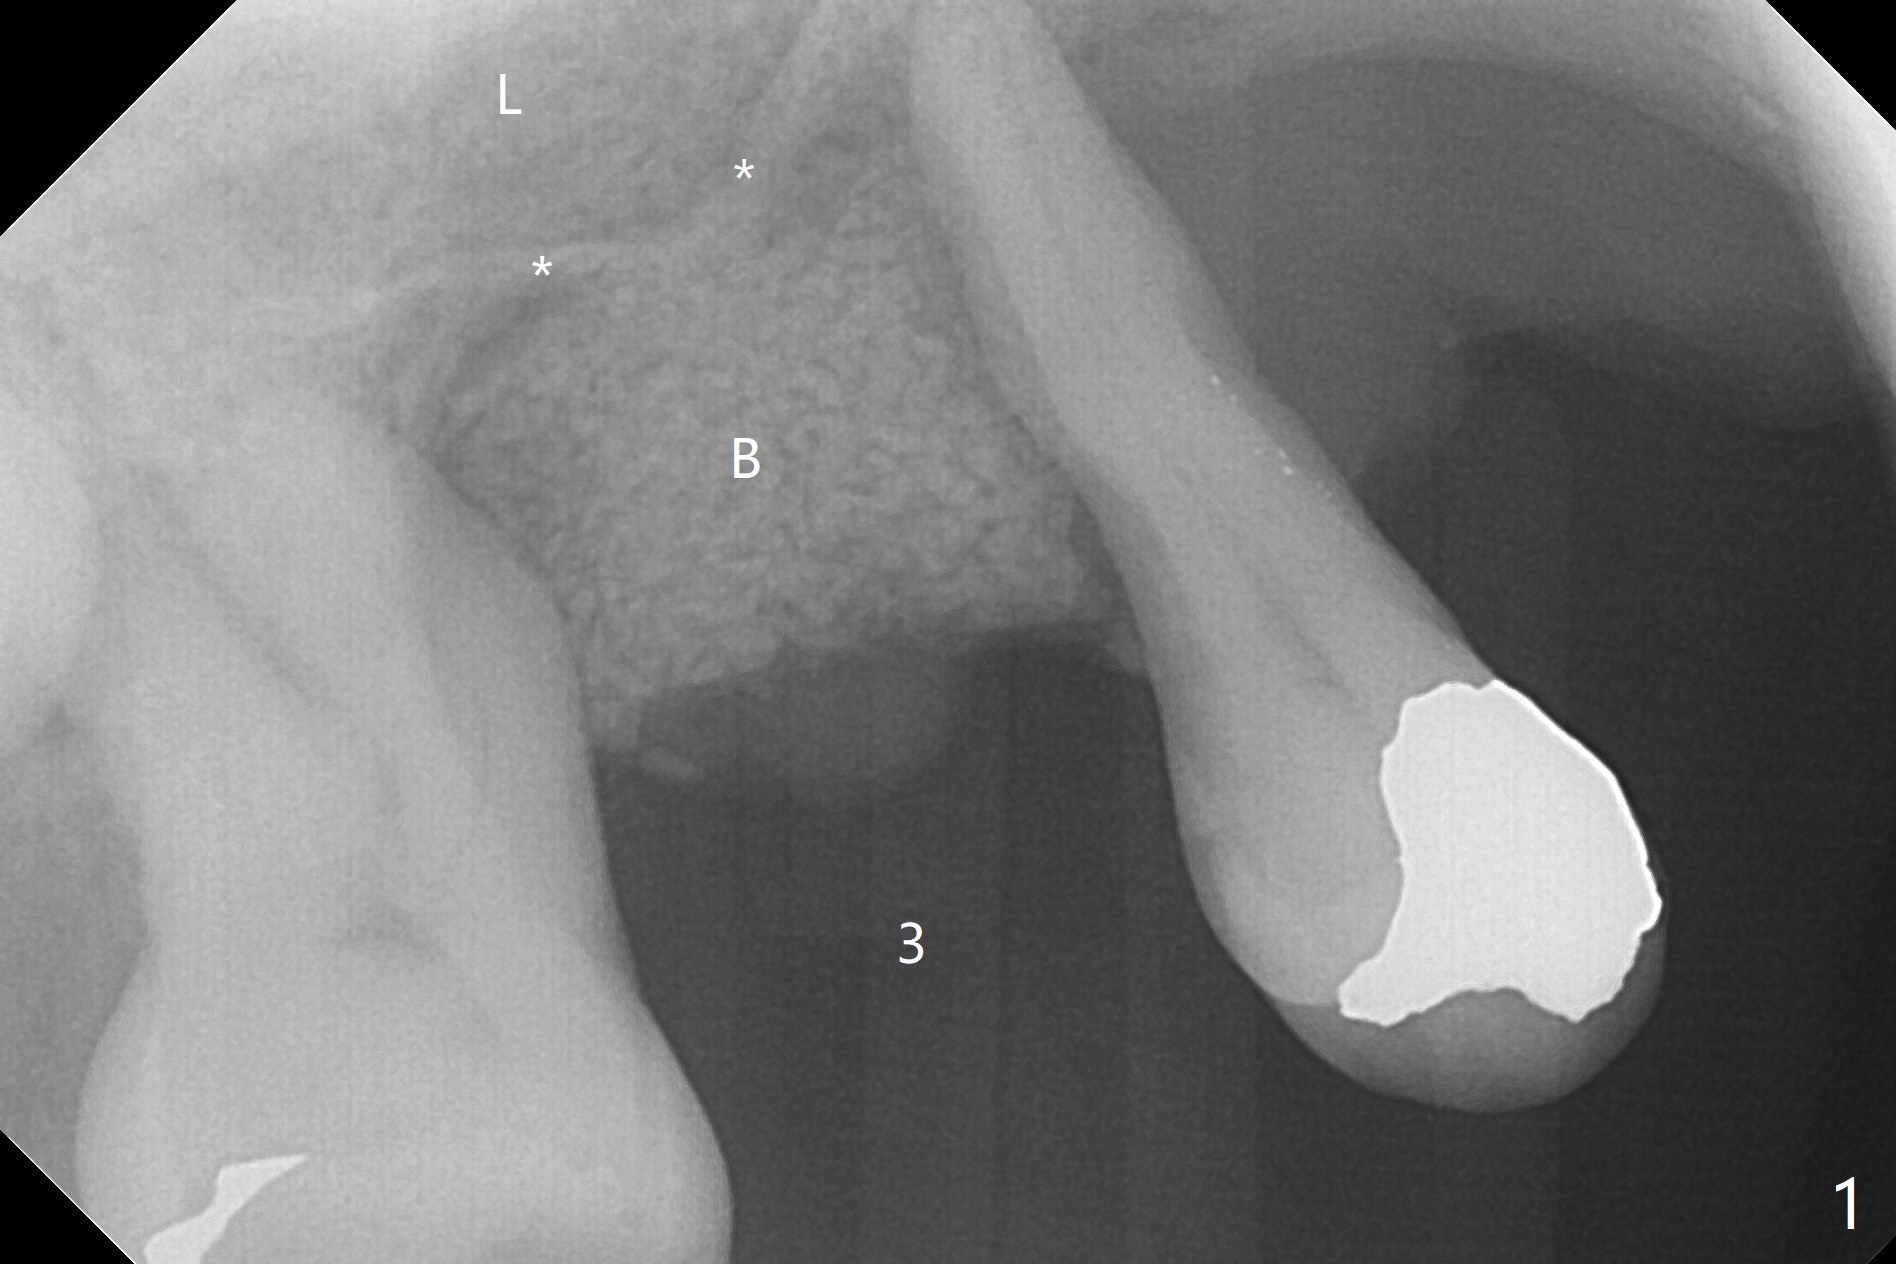

Since the tooth #3 has severe chronic periodontitis with 1 mm sinus floor (Fig.1 *), socket preservation may be not secure (B) in spite of using Cytoplast and PTFE suture. Prior to the bone graft, the sinus floor is lifted easily with Magic Sinus Lifter (IBS America) with Ossogen (mineralized cortical/cancellous (30%/70%) allograft, Fig.1,2 L). Periodontal dressing remains in place because of the neighboring teeth 1 week postop (Fig.3 D). Cytoplast remains in place after dislodgement of the periodontal dressing 2 weeks postop (Fig.4). Cytoplast dislodges 3 weeks postop (Fig.5). Socket preservation is not as secure as immediate implant in term of bone graft retention. What else can be done to prevent bone graft loss?